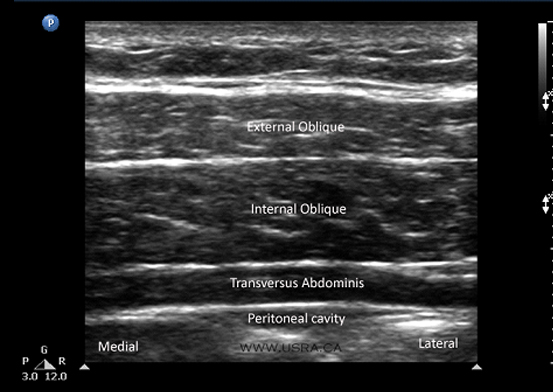

Carol eustice is a writer who covers arthritis and chronic illness. USRA - Transversus Abdominis Plane (TAP) Block

USRA - Transversus Abdominis Plane (TAP) Block from www.usra.ca